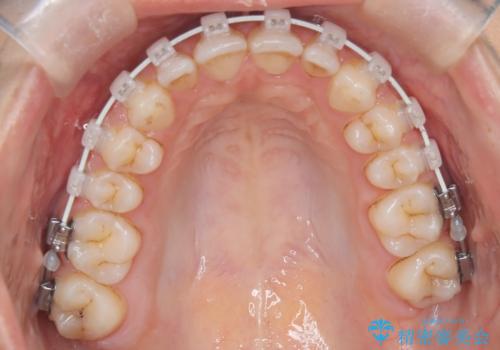

- 患者様は、前歯が出ている状態(上顎前突)と隙間を閉じたいというご希望で来院されました。診断の結果、骨格性の上顎前突が確認されたため、理想的には外科矯正が必要であることを説明しましたが、患者様の「非抜歯でできる範囲で治療を進めたい」という希望を尊重し、矯正治療計画を立てました。治療目標は、前歯の突出を可能な限り改善し、隙間を閉じることに重点を置きました。

本症例では、非抜歯での治療を選択したため、スペースを確保するためにIPR(歯間削合)を行い、歯列を整えました。オーバージェット(上の前歯と下の前歯の水平的なズレ)は残る結果となりましたが、見た目や機能の改善を重視し、患者様と治療計画を共有しながら進めました。治療中は、歯列全体のバランスと噛み合わせを考慮しつつ、矯正装置の適切な使用を徹底しました。当初の計画通りに治療を完了し、患者様にも満足していただけました。